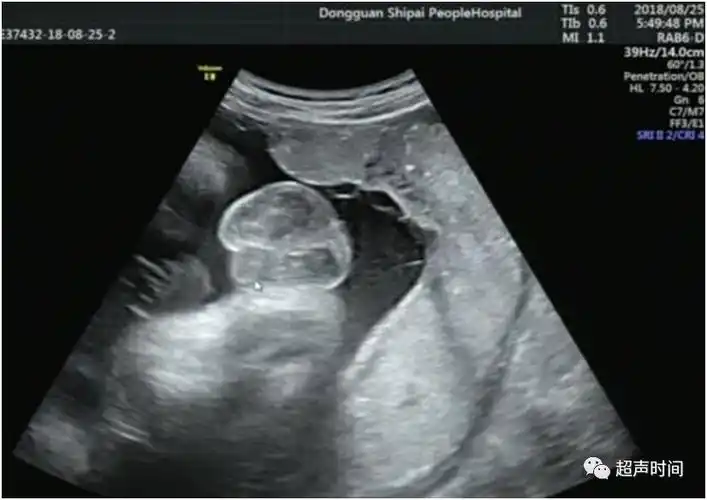

孕 周二维超声示胎儿男性外生殖器,呈「郁金香征」